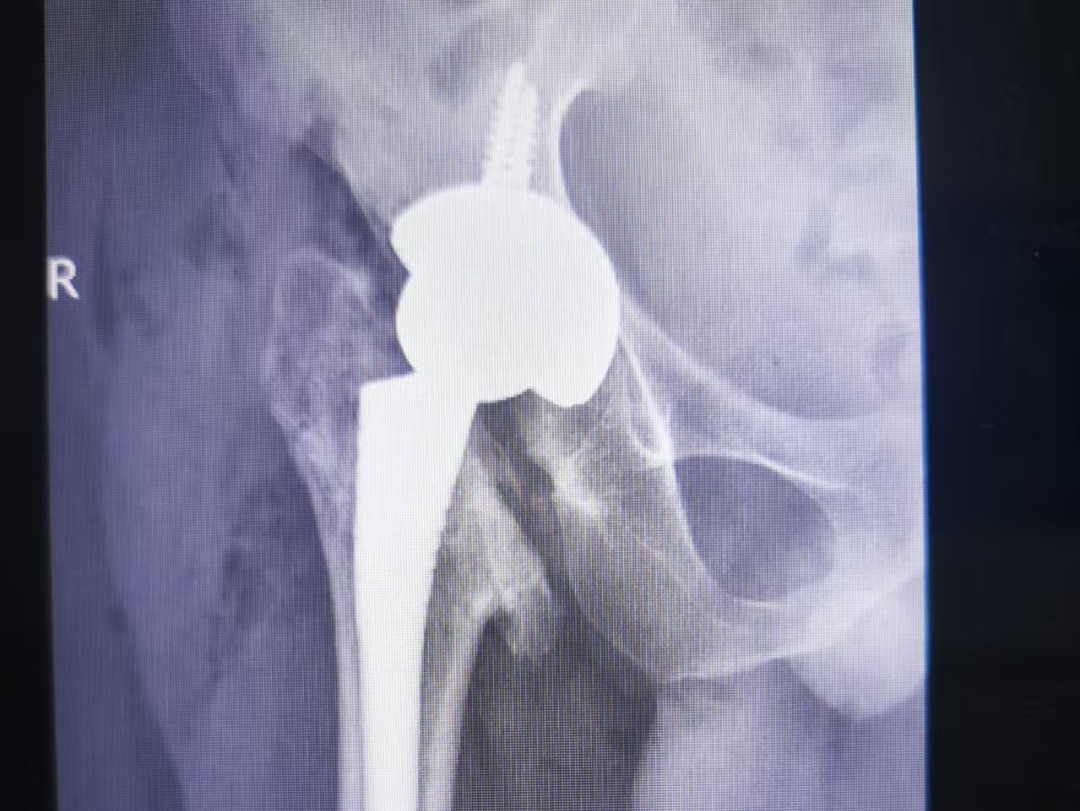

手术过程中,骨科团队全神贯注,先清除病变组织,重塑髋臼“骨窝”;接着精准植入人工关节,调整双腿长度;下移大结节,恢复肌肉发力点。术中出血仅300毫升,未输血。

术后次日,种先生疼痛大减。第二天,在医护人员的协助下,他借助助行器迈出第一步,激动地说:“腿终于听使唤了!这么多年了,我终于又能好好走路了!”复查显示人工关节位置精准,双腿等长,手术成功。